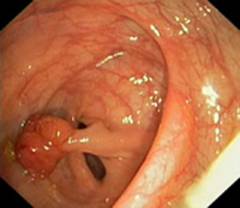

| Доброкачественная опухоль (полипы) | Полипы возникают из-за разрастания тканей, имеют различные размеры и формы. Обычно не проявляют себя клинически. | Примерно 60% доброкачественных опухолей могут перерасти в злокачественные, поэтому важно их выявление и удаление с помощью колоноскопии. |

| Полипы толстого кишечника | Изменения в обновлении клеток слизистой могут привести к образованию полипов, которые без лечения могут стать злокачественными. Колоноскопия позволяет их диагностировать и удалять. | Обычно без симптомов, иногда — кровотечение (кровь в кале). |